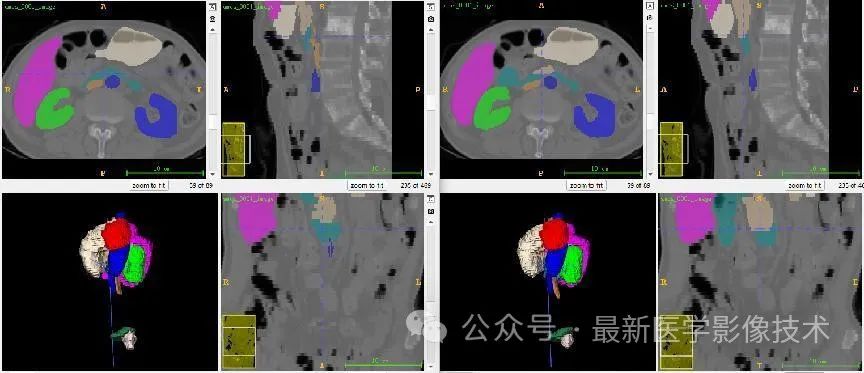

12、验证集分割结果

左图是金标准结果,右图是预测结果。